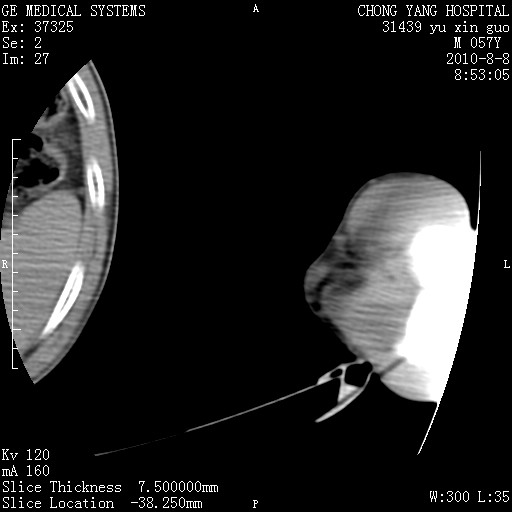

标题: CT28267:M57Y 上臂包块8年余。 [打印本页]

标题: CT28267:M57Y 上臂包块8年余。

包膜光滑、完整的脂肪密度肿块,支持脂肪瘤。